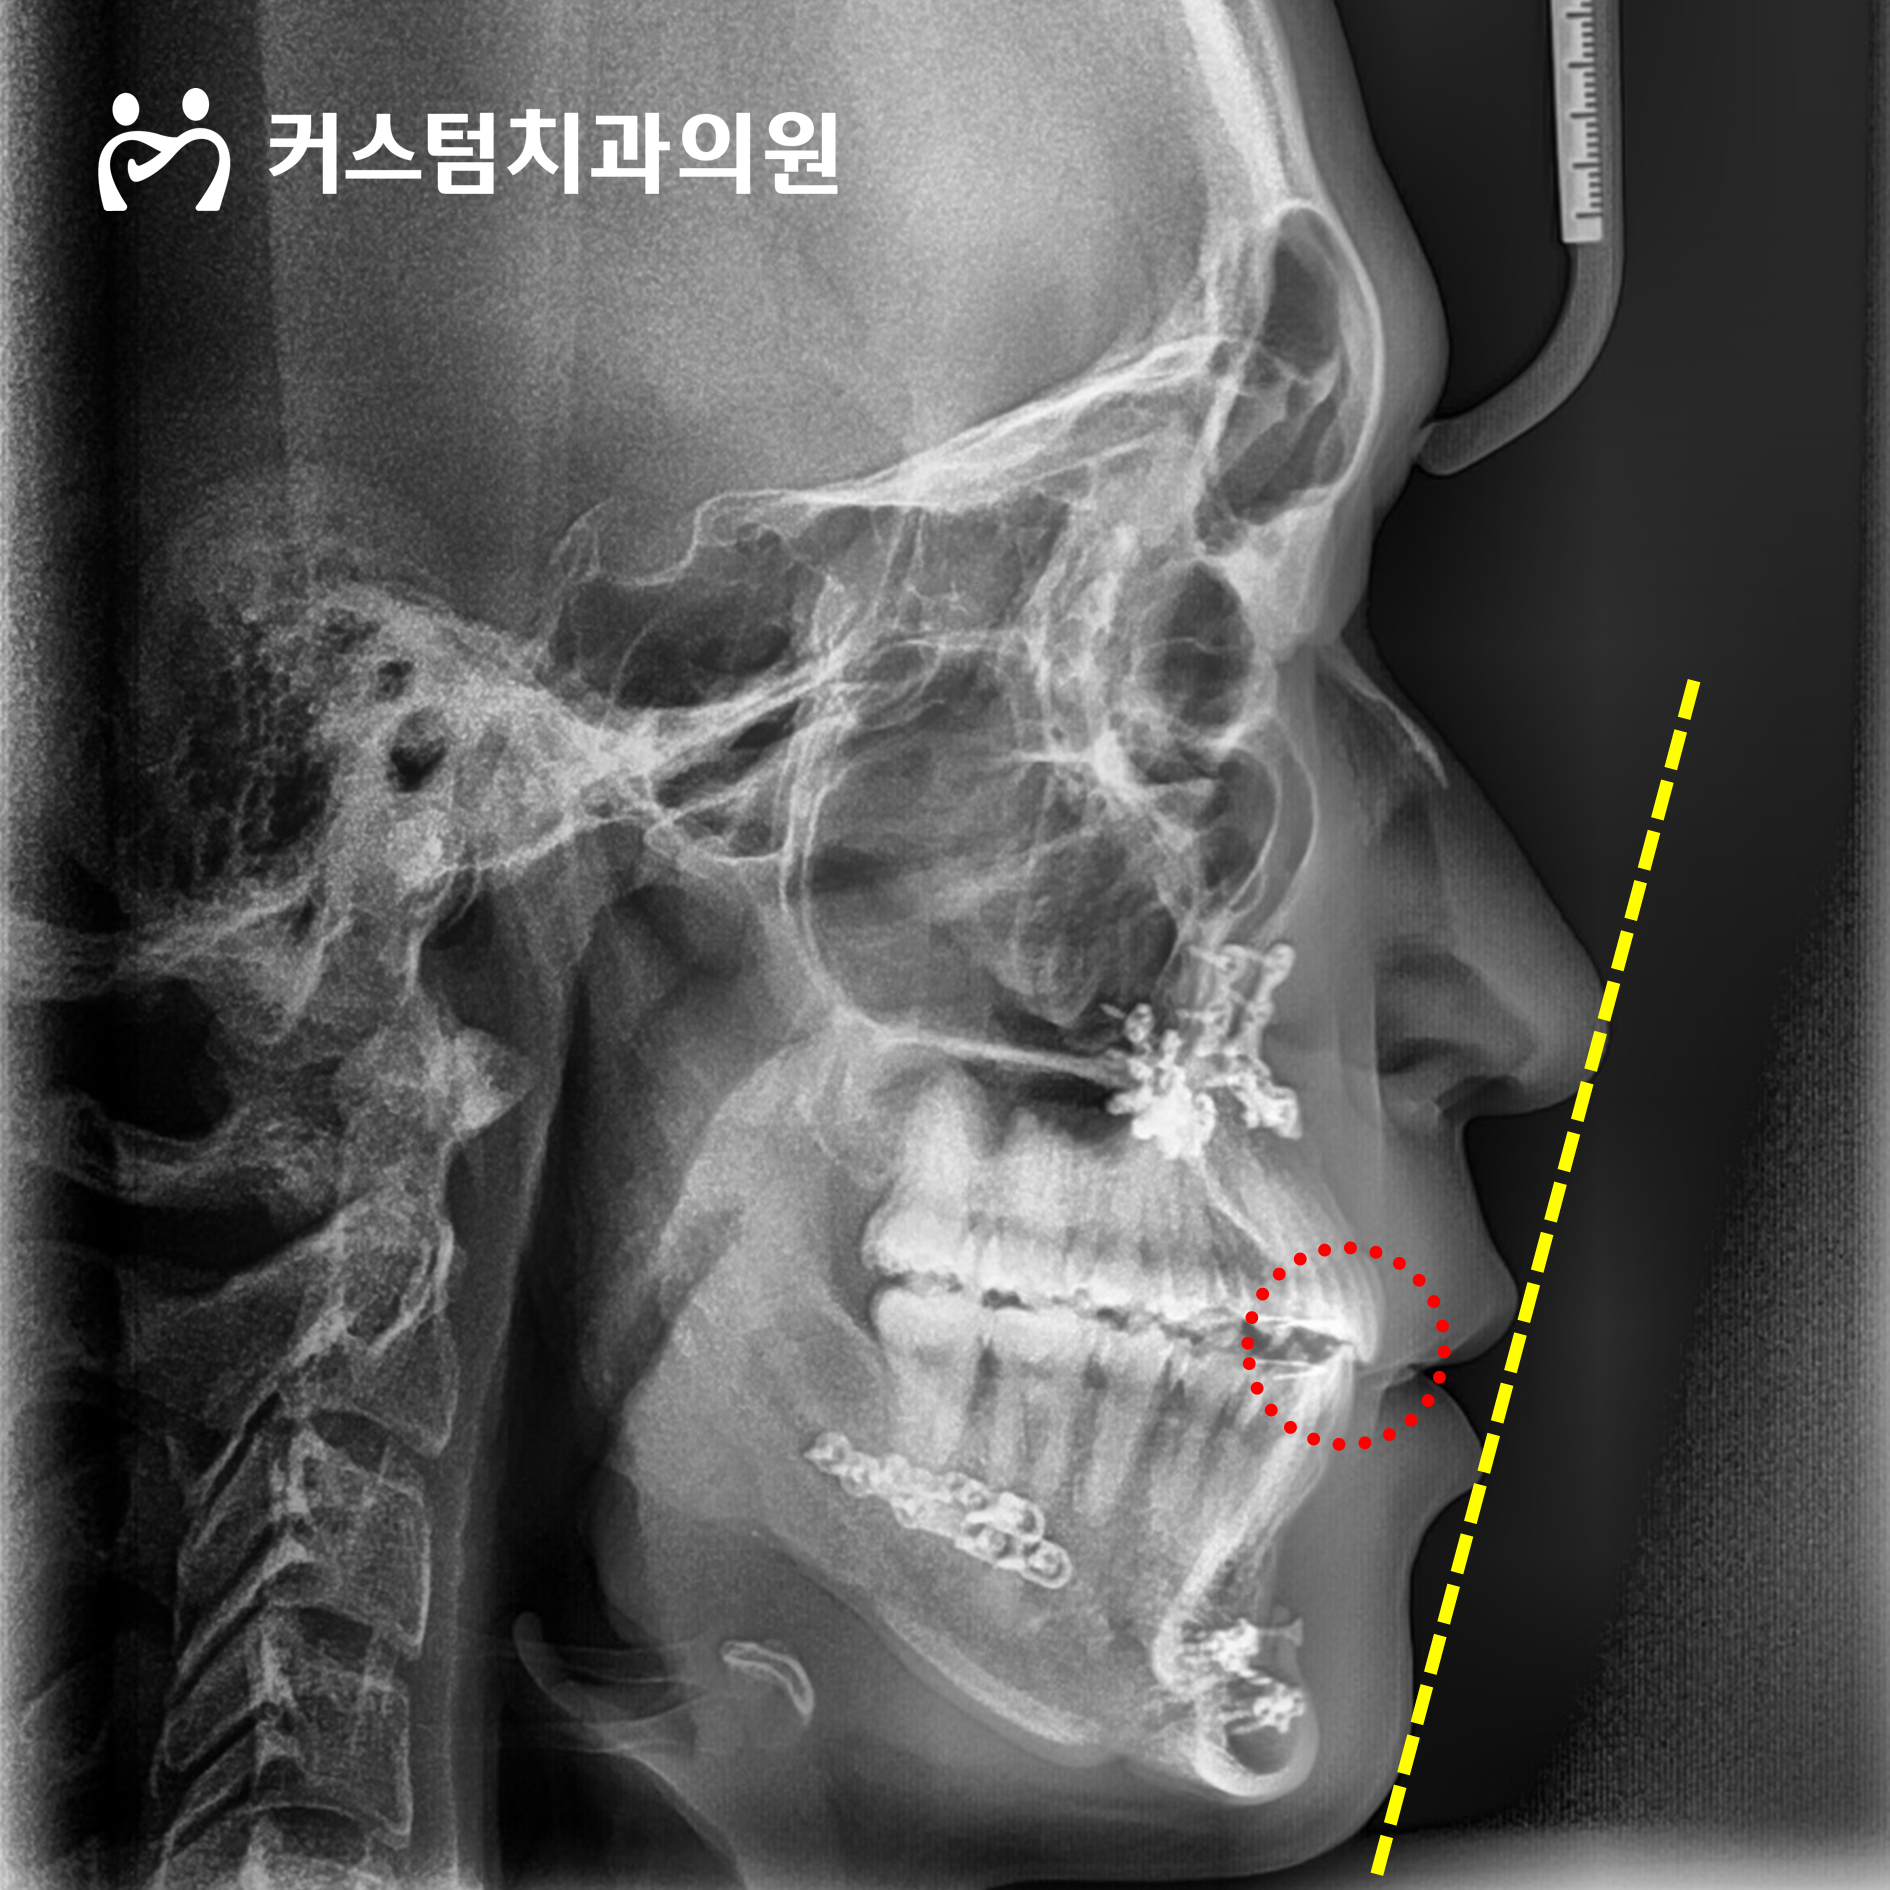

코끝에서 윗입술을 기준점으로 두고 가상의 직선을 그어 판단하였을 때, 주걱턱이 심한 수준으로 보였습니다.

하악의 크기가 상악보다 큰 편이며, 위치도 비교적 앞쪽에 있었습니다. 유년기 골격성장에 있어 상하균형이 제대로 이루어지지 않았다는 점을 어느 정도 짐작할 수 있었습니다.

이런 요소가 기능적인 측면에서도 부정적인 요소로 작용한다는 점을 추가적으로 확인할 수 있었습니다.

앞니가 서로 거꾸로 맞물려 있는 반대교합 양상이 뚜렷한 편이었고, 어금니도 엉성하게 물리는 편이라 그간 저작활동을 수행함에 있어서 어려움이 있겠다고 짐작됐습니다.